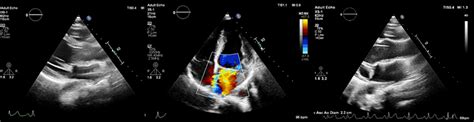

To diagnose the extent of the dilation, clinicians utilize non-invasive imaging techniques. An echocardiogram is the primary tool used to measure the diameter of the aortic root. If further detail is required, a cardiac CT scan or MRI provides a comprehensive three-dimensional view of the aorta, allowing surgeons to plan potential interventions.

Echocardiogram Measure aortic root diameter Annual or biannual